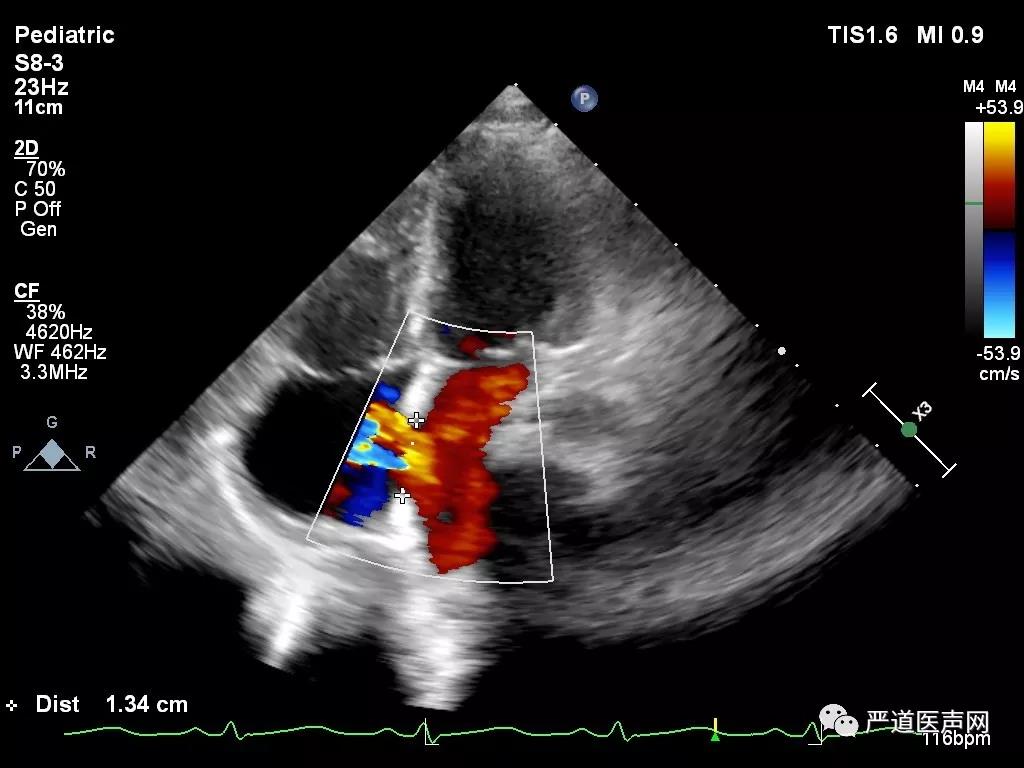

术前超声测量

术中超声显示:房间隔缺损,继发孔型,大小12mm,右心导管检查提示Qp/Qs:1.45,肺动脉压力28/9 (18)mmHg,建立钢丝轨道,选择6F MPA2导管,经房间隔缺损送入左房,置于左上肺静脉,并导入输送钢丝0.035/260cm。